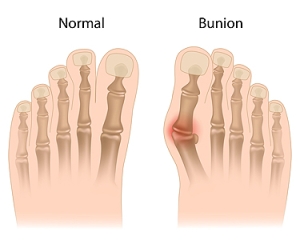

Various Types of Bunions and Different Treatments

Bunions may appear in several ways, each with its own challenges. Some are mild and cause only slight irritation, while others are moderate and with them, the big toe is pushed inward. Severe bunions can create significant pain and limit daily activities. A bunionette, also known as a tailor’s bunion, forms on the outside of the foot near the little toe. Juvenile bunions often develop in younger people and are usually linked to inherited foot structure. Treatment options vary depending on how advanced the bunion is. Simple changes such as wearing wider shoes, applying padding, or using custom orthotics can relieve pressure. More serious bunions may require surgery to correct the alignment and ease discomfort. If you notice a bunion is starting to affect your comfort or mobility, it is suggested that you see a podiatrist who can provide the right diagnosis and treatment plan.

What Is a Bunion?

Bunions are painful bony bumps that usually develop on the inside of the foot at the joint of the big toe. As the deformity increases over time, it may become painful to walk and wear shoes. Women are more likely to exacerbate existing bunions since they often wear tight, narrow shoes that shift their toes together. Bunion pain can be relieved by wearing wider shoes with enough room for the toes.

Causes

- Genetics – some people inherit feet that are more prone to bunion development

- Inflammatory Conditions - rheumatoid arthritis and polio may cause bunion development

Symptoms

- Redness and inflammation

- Pain and tenderness

- Callus or corns on the bump

- Restricted motion in the big toe

In order to diagnose your bunion, your podiatrist may ask about your medical history, symptoms, and general health. Your doctor might also order an x-ray to take a closer look at your feet. Nonsurgical treatment options include orthotics, padding, icing, changes in footwear, and medication. If nonsurgical treatments don’t alleviate your bunion pain, surgery may be necessary.

What Are Bunions?

Bunions are large bony bumps at the base of the big toe. Medically known as hallux valgus, a bunion is a misalignment of the metatarsophalangeal joint, or big toe joint. The misalignment will generally worsen with time if left untreated.

The exact cause of bunions is unknown, with genetics seen as a potential cause. High heels and poorly-fitted footwear, rheumatoid arthritis, and heredity all seem to be potential factors behind the exacerbation of bunions. Women have been found to be more likely to develop bunions in comparison to men.

Bunions do not always produce symptoms. The best way to tell is if the big toe is pushing up against the next toe and there is a large protrusion at the base of the big toe. You may or may not feel pain. Redness, swelling, and restricted movement of the big toe may be present as well.

Podiatrists use a variety of methods to diagnose bunions. If there are symptoms present, podiatrists will first consider that it is a bunion. If not, a physical examination will be conducted to check function of the big toe. Finally, an X-ray may be taken to view the extent of the bunion and confirm it is a bunion.

Typically, nonsurgical methods are used to treat bunions, unless the bunion has become too misaligned. Orthotics, icing and resting the foot, roomier and better fitted shoes, taping the foot, and pain medication are usually utilized first. If the bunion doesn’t go away or causes extreme pain, surgery may be required. Surgeons will either remove part of the swollen tissue or bone to straighten the toe out.

If you have a bunion, it is recommended to see a podiatrist. The longer it is left untreated, the worse it may get. Podiatrists can properly diagnose and treat a bunion before it gets worse.